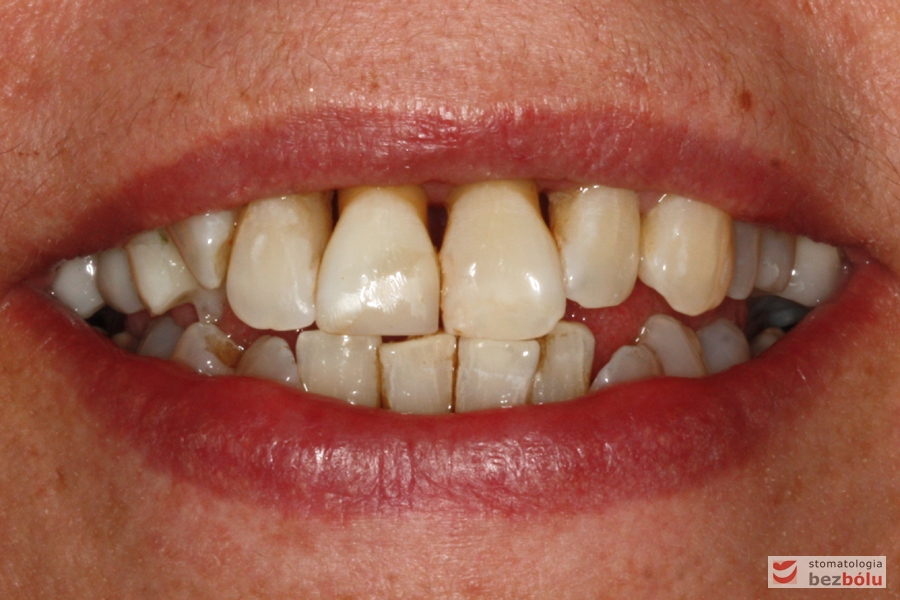

Pani w średnim wieku ze świadomością deficytów estetycznych uzębienia, zgłosiła się celem uporządkowania jamy ustnej. Swoje oczekiwania opierała na doświadczeniu lekarza prowadzącego. Co unikalne w obecnych czasach nie naciskała na tempo leczenia i chciała metodycznie doprowadzić swoje uzębienie do optymalnego stanu. Główną skargą były wydłużone siekacze centralne, stłoczenia, dyskoloracje i cechy choroby przyzębia.

Zęby w zwarciu - widok frontalny, zgryz krzyżowy w pozycji kłów, paradontalny status siekaczy

Zęby w zwarciu – widok frontalny, zgryz krzyżowy w pozycji kłów, paradontalny status siekaczy